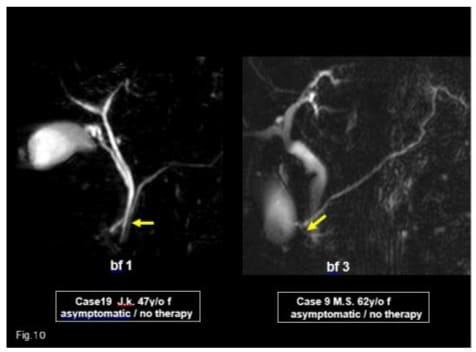

Recently usefulness of MRCP is reported in diagnosis of IPD [9,10]. In our series, MRCP was performed in 57 cases-49 cases (89%) could be diagnosed correctly, and 20 cases were diagnosed by MRCP alone (Figure 10). More IPD cases will be reported by MRCP diagnosis in the near future. We had no case of cancer occurrence. Kamisawa reported that the cancer occurrence rate was 9% (4/44)in complete and incomplete divisum, mainly in dorsal duct [6,11].